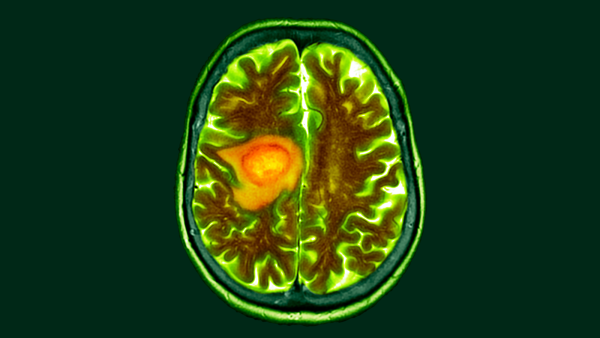

Наночастинки — жовті цятки — можна розробити так, щоб вони націлювалися на ракові клітини, які мають синій колір.